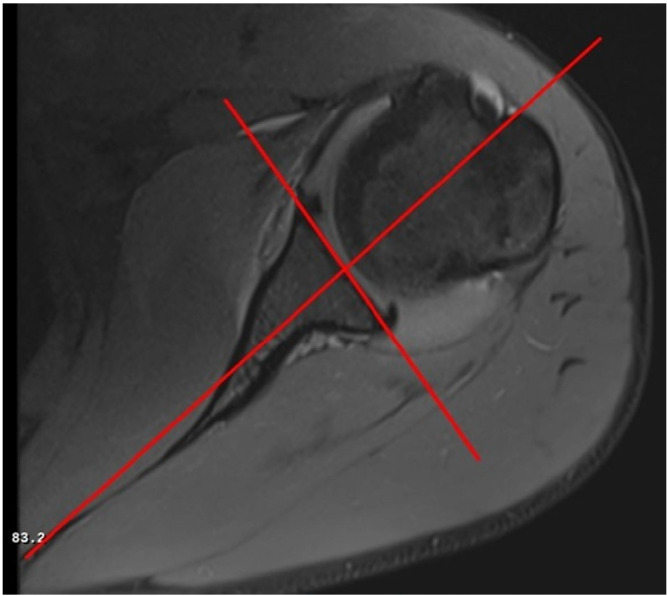

Methods: This study included 72 patients who underwent surgery for ASI and 72 age- and sex-matched controls. The sagittal central glenoid- coracoid angle (scGCA) and axial central glenoid-coracoid angle (acGCA), which assess the coracoid apex position relative to the glenoid center, the glenoid version (GV), and glenoid inclination (GI) were evaluated using magnetic resonance imaging. The critical shoulder angle (CSA) was measured using true anterior-posterior radiographs.

Abstract Image